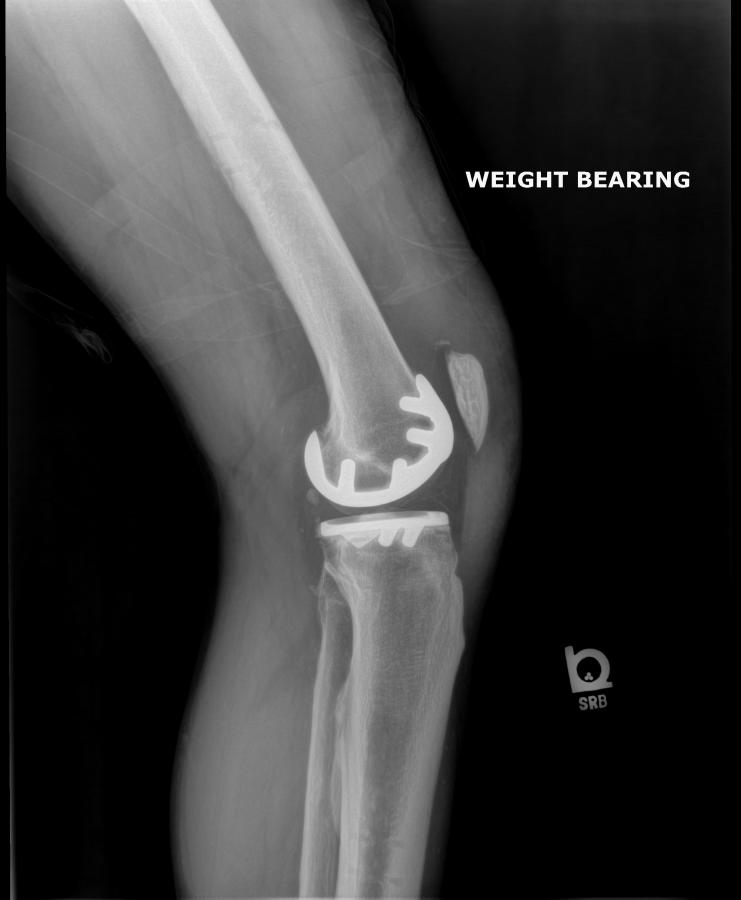

After – Left Knee

After - Left Knee Cap

After - Left Knee-Front